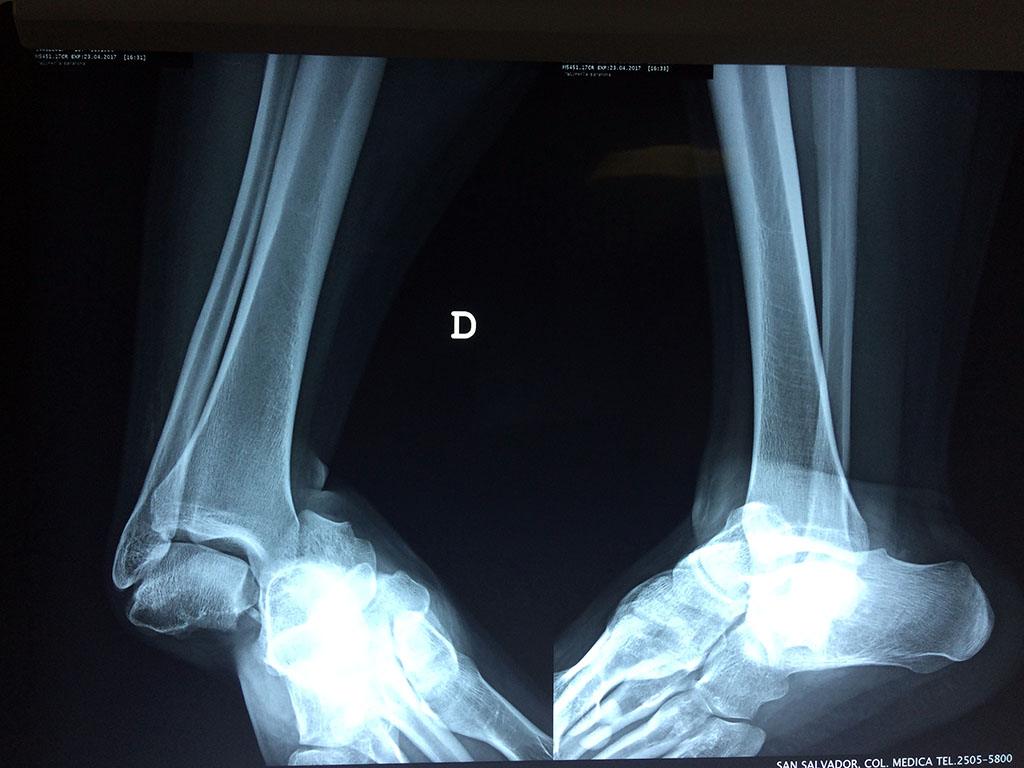

Una fractura de tobillo es la rotura de uno o más de los huesos del tobillo. Estas fracturas pueden ser:

• Completas (el hueso está perforado y está en 2 partes).

• Producirse en uno o ambos lados del tobillo.

Astrágalo Tobil...

Detail Download